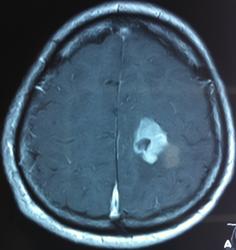

Начало вот здесь http://www.radiomed.ru/cases/kt-gms-obemnoe-obrazovanie-levoi-gemisfery-bolshogo-mozga-vnutrizheludochkovaya-meningioma. Пациент оперирован (меня сначала дезинформировали по поводу операции), перед операцией состояние ухудшилось, возникла правосторонняя гемиплегия, которая осталась и после декомпрессии. МРТ, КТ снимки и выписку предоставила супруга пациента, снимал на iphone, простите за качество, дисков с исследованиями не записывали. Надеюсь вопрос по данному случаю исчерпан.

Вот "цветочки":

Т2

И Вы считаете, что эта опухоль имеет интравентрикулярную локализацию?

Изначально по КТ я так предпологал, а теперь на 100% уверен, разве МРТ это не показало? Гистологически - менингиома, опухоль мозговой оболочки. Покажите, пожалуйста, образование где-нибудь прилежит к костям, где есть мозговая оболочка? Я не вижу, зато отчетливо вижу в левом боковом желудочке из оболочек сосудистого сплетения. Что вас еще смущает? По-моему, предостаточно фактов, чтобы развеять все сомнения.

Мне видится так. Иначе в данной локализации просто неоткуда расти оболочечной опухоли. На контрольной КТ, после декомпрессии, когда срединные структуры стали действительно срединны, правое обызвествленное сосудистое сплетение видно отчетливо, а левое, где оно? Ведь если бы образование компремировало, то после операции, когда часть мозга пролабировало в трепанационное отверстие мы бы увидели и левое сосудистое сплетение, но оно интимно связано с образованием и даже "потянулось" за ним в сторону декомпрессионного отверстия, потому что это и есть "росток" откуда выросла опухоль.